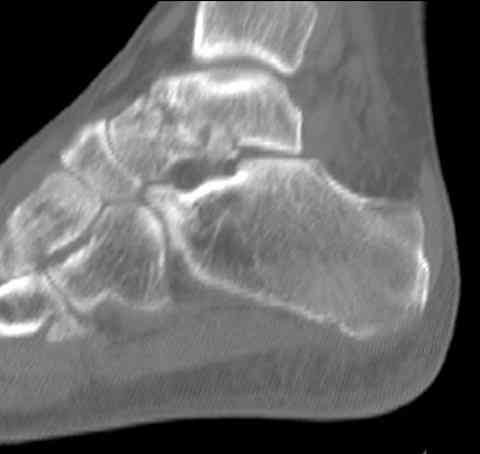

Случай с множественным оскольчатым переломом тарана оперированный из двойного доступа.

Через 8 мес.: